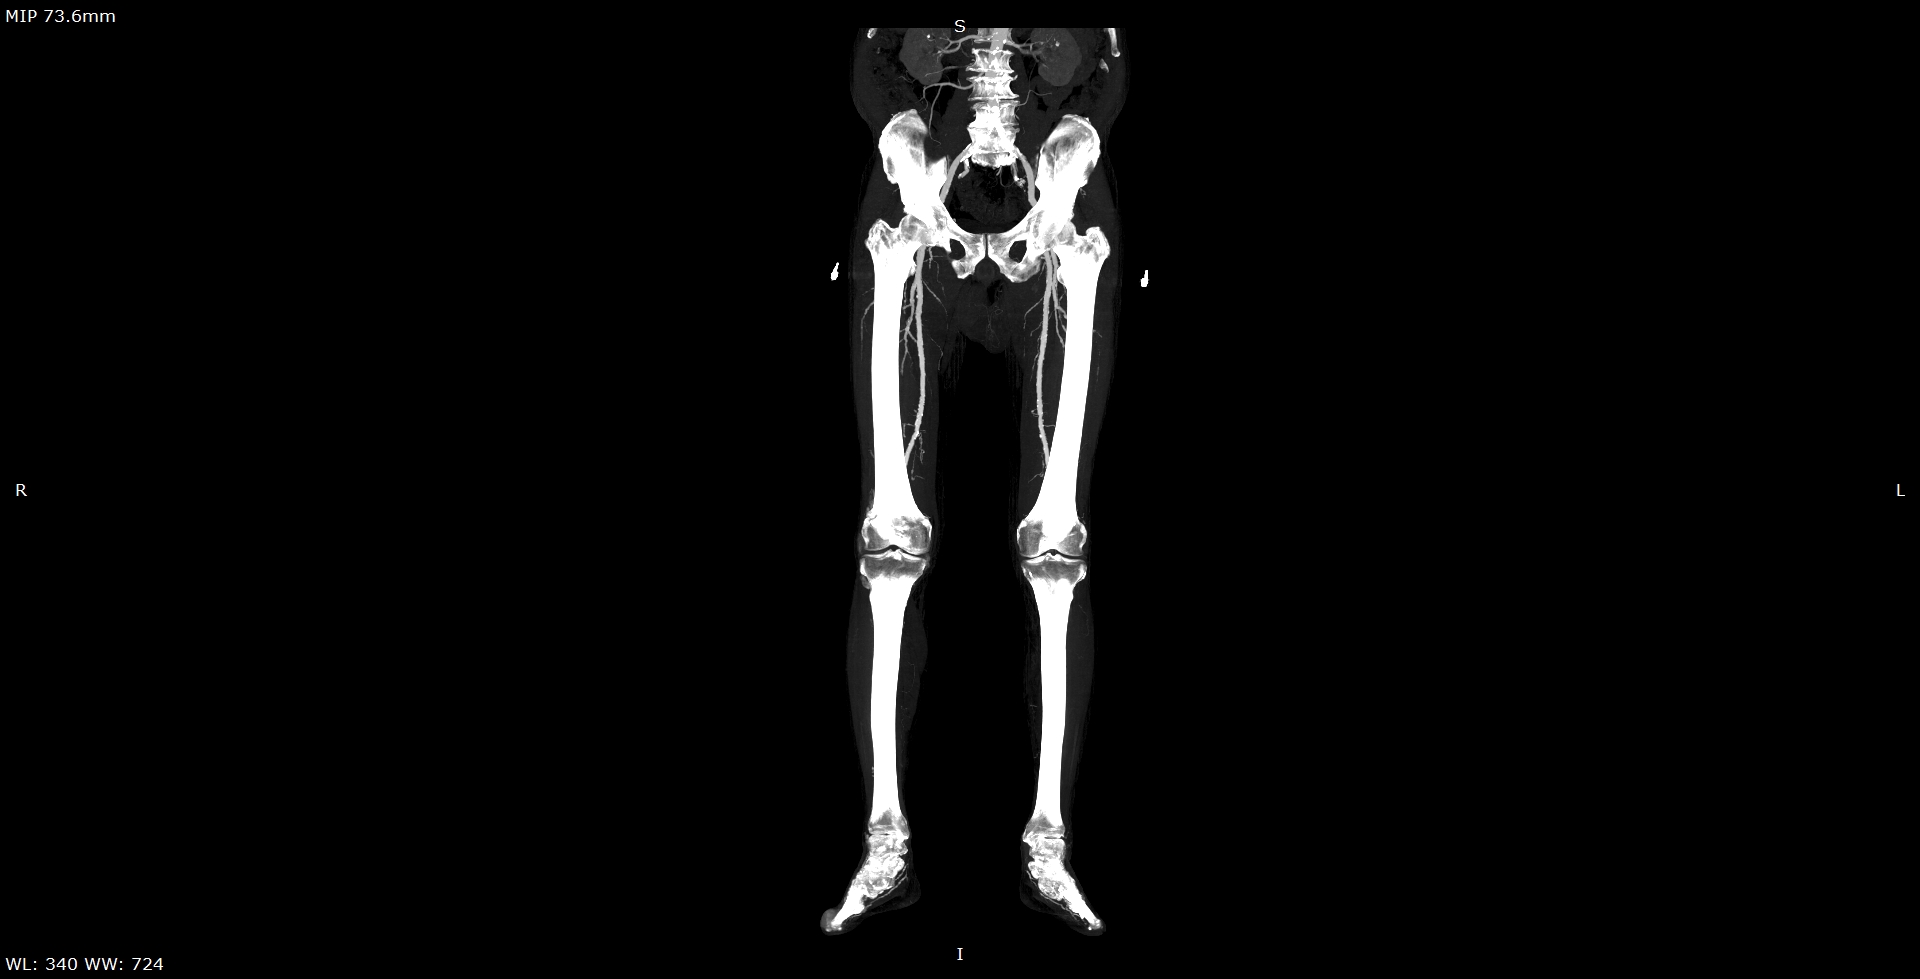

Мультиспиральная компьютерная томография является современным методом обследования сосудистой системы нижних конечностей. Такое исследование по-другому называется КТ-ангиография. Методика позволяет с помощью рентгеновского излучения получить посрезовые снимки и после цифровой обработки создать объемные модели кровеносной системы обеих ног.

В наших медицинских центрах КТ-ангиография нижних конечностей выполняется на современных мультиспиральных компьютерных томографах экспертного уровня TOSHIBA AQUILION. Аппараты послойно сканируют область исследования, одномоментно выполняя множество тончайших срезов. В результате получаются снимки высокого качества и трехмерные модели с изображением даже мелкой сосудистой сети нижних конечностей. При этом методика скоростного мультисрезового сканирования обеспечивает минимальную дозу рентгеновского облучения для пациента.

• КТ сосудов от бифуркации аорты до коленного сустава (оценивается нижняя часть брюшной аорты, разветвление аорты, подвздошные артерии, бедренные и подколенные артерии)

• КТ сосудов от бифуркации аорты до стопы (данный протокол обследования включает в себя полное обследование сосудов нижних конечностей, включая стопы)